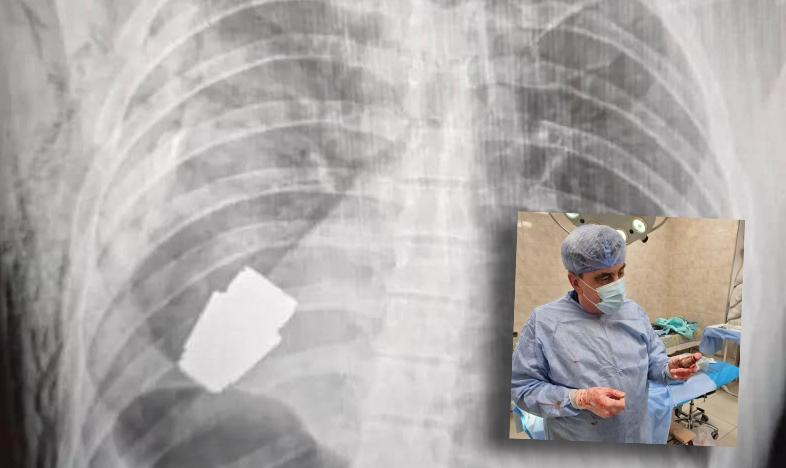

Il 9 gennaio 2023, la viceministro della difesa dell’Ucraina Hanna Maljar postava su Facebook la radiografia di un militare ucraino in cui si vedeva una cosiddetta granata VOG inesplosa alloggiata dentro il petto e vicino al cuore. Questi piccoli ordigni di dimensioni di circa quattro centimetri vengono sparati in serie con il lanciagranate GP-25 in dotazione all’esercito russo, arma che ha l’aspetto di un fucile ed è efficace a partire dai 400 metri di distanza dal bersaglio.

Tutti con il fiato sospeso, dunque, finché Anton Jurijovyč Geraščenko, consigliere del Ministro degliinterni molto attivo sui social, non ha postato una foto del chirurgo Verba con i guanti ancorainsanguinati e la granata ancora inesplosa nel palmo della mano. Il commento era: «Granata estratta appena sotto il cuore, non esplosa ma ancora esplosiva. Mai successo nella storia della medicina di dover effettuare una tale operazione».